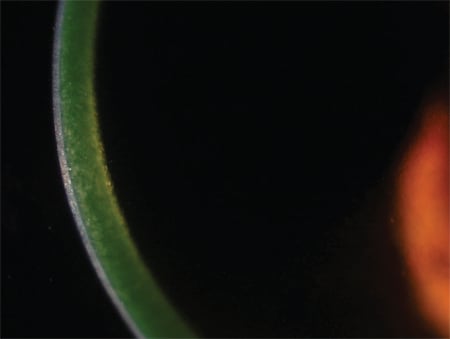

Slit-lamp photo of riboflavin loading during epi-on CXL shows good saturation.